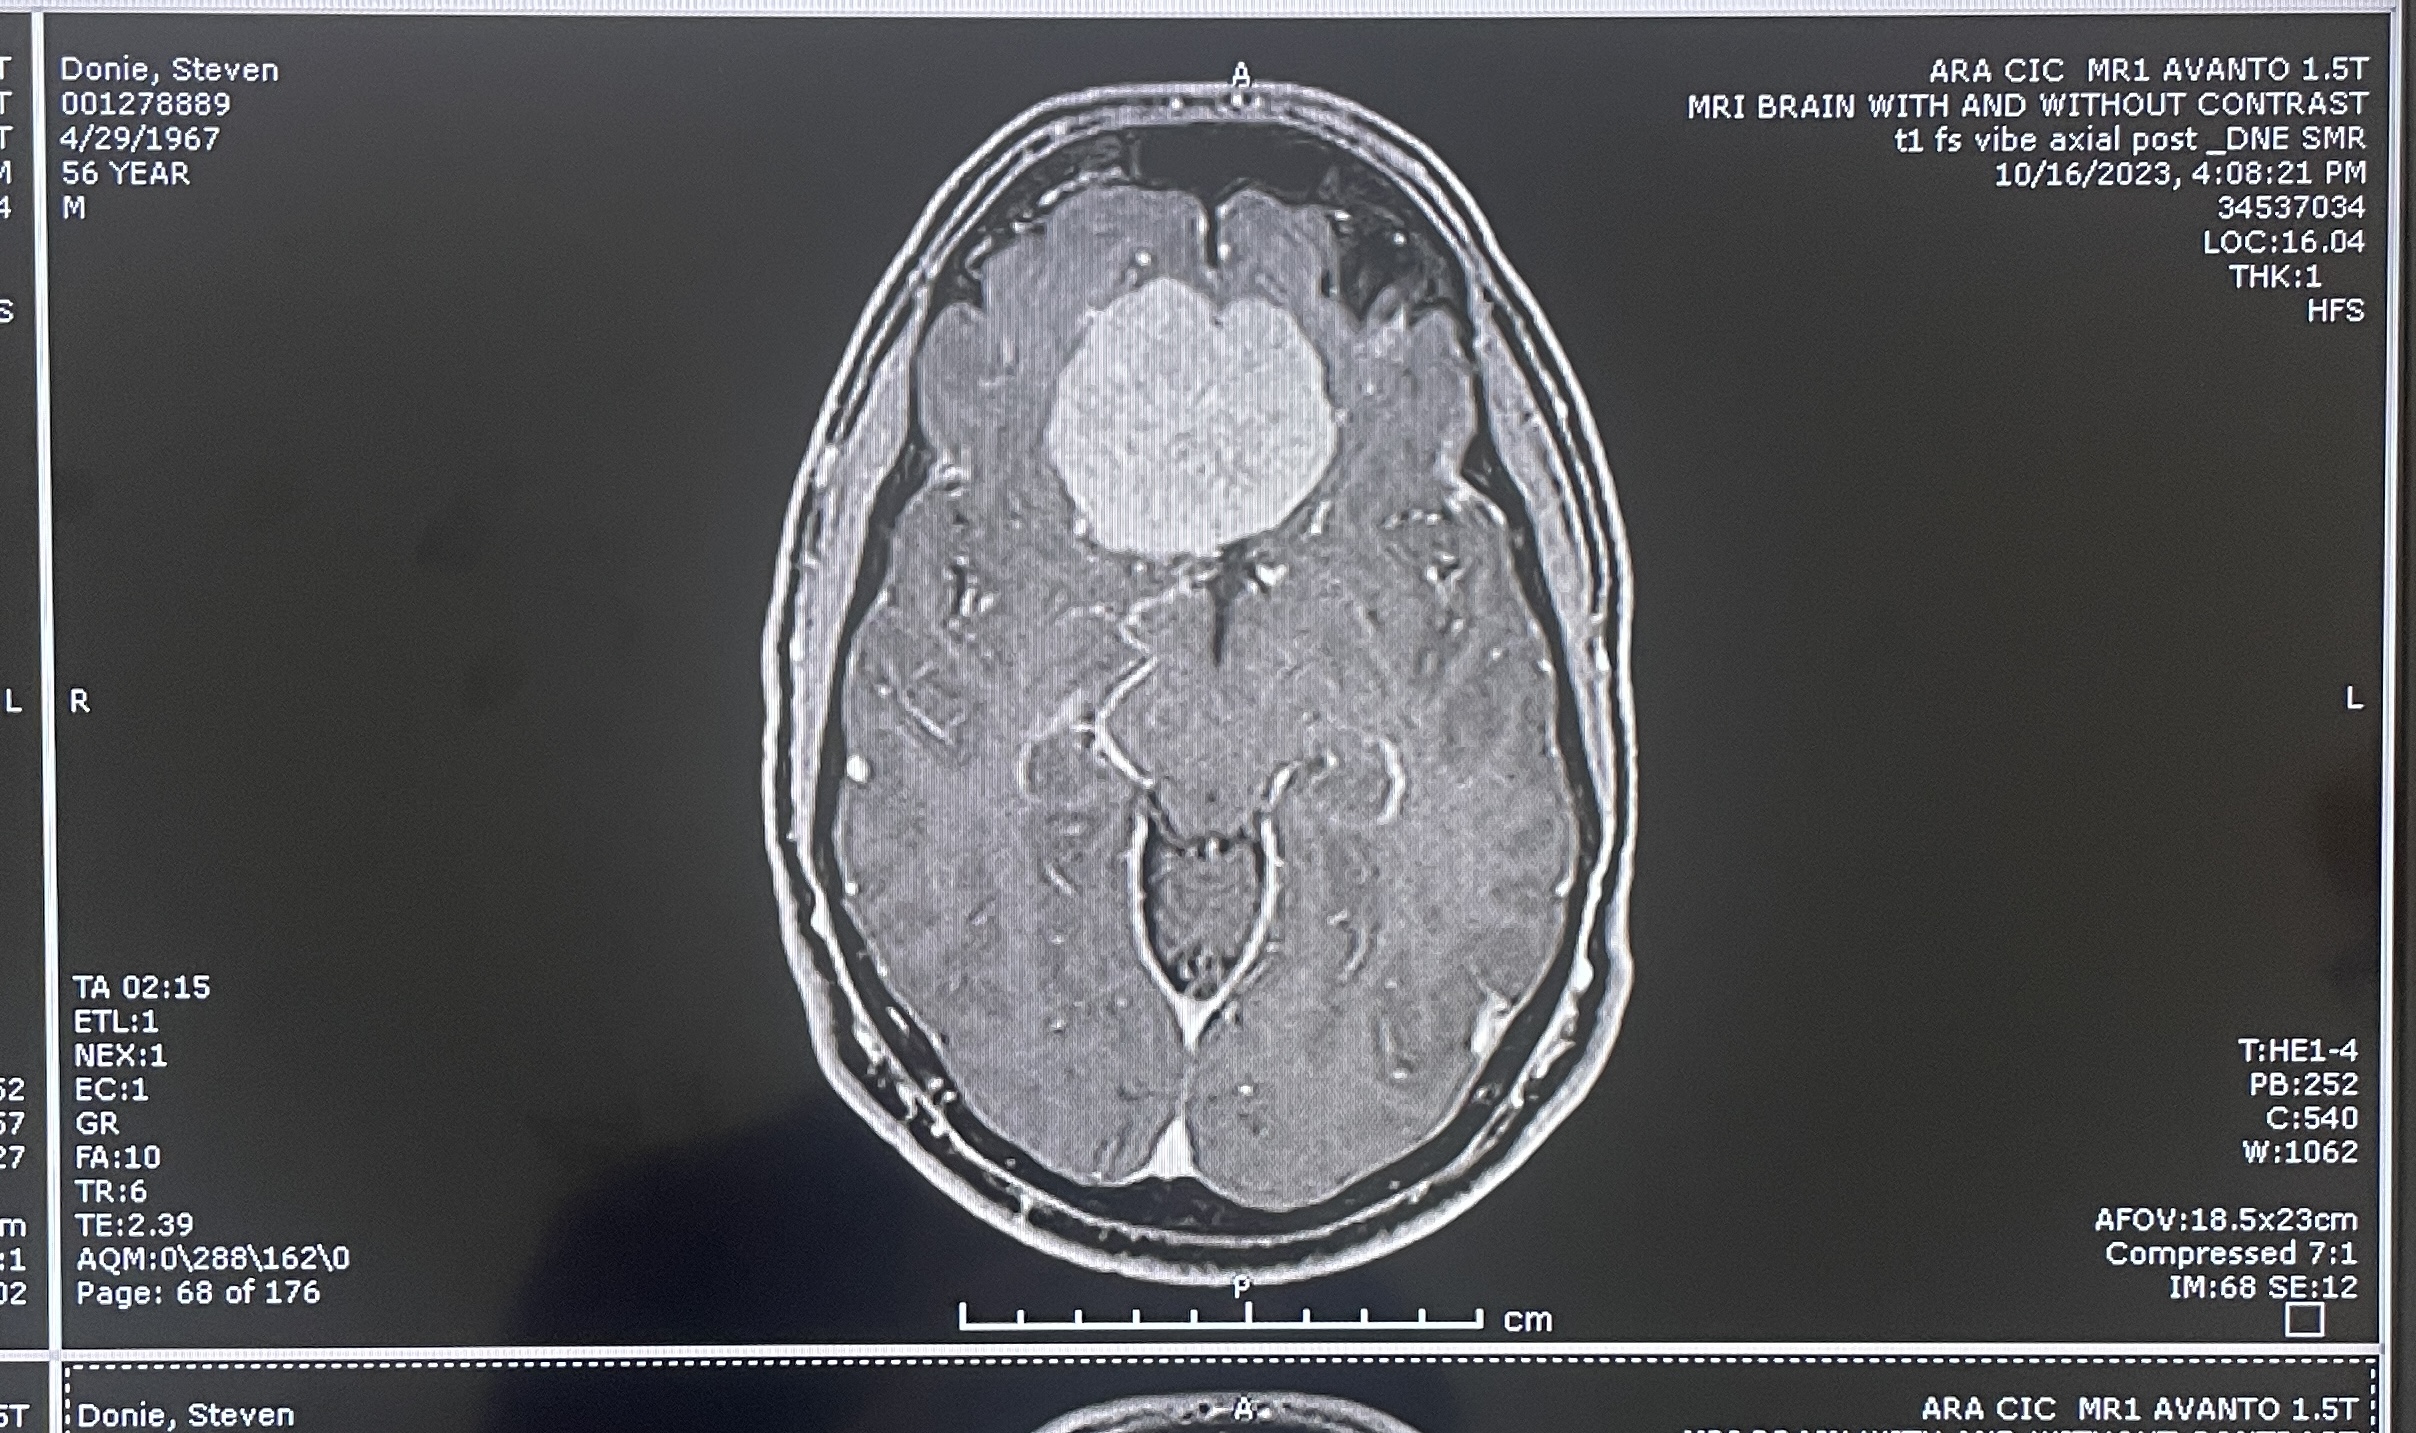

MRI, front and side views

Another clear top view

more MRI